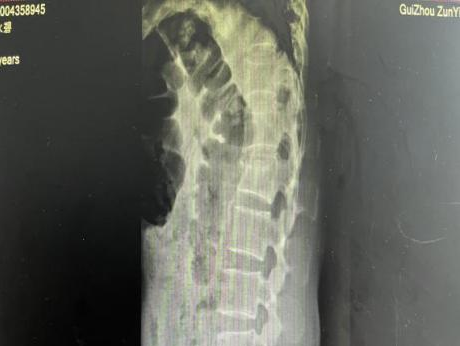

多年来,贵州航天医院各科室紧跟医学前沿,不断强技术、补短板,大力开展新技术、新项目,完成了许多高精尖、高难度、本地区“首例”的技术,填补了医院医疗技术空白,满足了群众日益增长的医疗需求。 贵州航天医院骨科率先在遵义地区开展骨搬移技术,截至目前,已治愈慢性骨髓炎、感染性骨不连、骨缺损、脉管炎、糖尿病足患者200余例,糖尿病足治疗保肢率达到98%。 本期,我们将为大家带来骨科特色技术——骨搬移技术(Ilizarov)。 案例分享 一名59岁的患者,身患糖尿病12年,在来我院3个月前出现了右脚溃烂的症状,来院就诊时,患者的右脚十分红肿,右脚脚趾坏死,伤口处不断流出黑红色脓液,情况十分严重。在接诊到患者时,骨科专家团队高度重视,立刻为患者完善了CT血管造影(CTA)等相关检查,诊断为:2型糖尿病,糖尿病周围血管病变,右糖尿病足。 术 前 考虑到患者情况比较严重,为最大限度保证患者肢体完整,科室专家团队进行了严格的讨论评估,为患者制定了骨搬移技术治疗方案,在征得患者及其家属的同意后,成功通过搬移骨块为患者进行治疗,促进患者病变肢体血管再生。 胫骨横向骨搬移外架固定 清除感染病灶 术后调节外架,通过搬移骨块 促进患肢血管再生 患者在术后三周前来换药,观察到感染得到进一步控制;术后六周复查,患者病变处已愈合,进行CT血管造影(CTA)后可明显观察到足部血管再生。 术后3周 术后6周愈合 CT血管造影见足部血管再生 糖尿病患者全身与局部的问题互为影响,形成恶性循环,糖尿病足溃疡创面迁延不愈,常见干性坏疽、湿性坏疽、趾坏死、深且大的溃疡以及骨髓炎等症状,还可导致脓毒血症,以往为保全生命,患者被迫选择一次或多次截肢。骨搬移技术的发展进步,能在血糖有效控制、局部有效清创下,有效促进患肢微血管再生,改善患肢血供,达到糖尿病足更快治疗康复的目的,并能根据病变情况最大限度的保障患者肢体完整。 什么是骨搬移技术 骨搬移技术是通过使用专用的骨外固定器固定骨段,每天缓慢牵拉,在牵拉搬移过程中,骨段尾部形成新骨及新的软组织,从而修复骨骼缺损及软组织缺损。是治疗大段骨缺损、骨不连、骨感染、肢体畸形的金标准方法,也用于治疗脉管炎、糖尿病足等肢体缺血性疾病。 骨感染缺损 切除感染段 搬移骨段 新骨形成 骨感染根治愈合 骨搬移技术原理 生物组织在持续、稳定、缓慢牵拉下,能刺激细胞分裂、组织再生,骨外固定技术运用该原理,通过持续缓慢调节外固定器形成牵拉张力,促进牵引成骨与相邻组织再生,如神经、血管、肌肉、皮肤等再生,达到治疗大段骨缺损、肢体缺血如糖尿病足等疾病的目的。 骨搬移技术优势 (一)除治疗骨缺损、骨不连外,有更广的适用范围,利用组织再生、血管再生等特性,能大量运用于肢体畸形的矫形、糖尿病足等的治疗。 (二)治疗效果确切,重建肢体外型和功能,极大降低截肢率和残疾率。 (三)明显提高了患者生活质量,极大减轻其家庭及社会负担。 肢体畸形的矫形 慢性骨髓炎 骨段切除 术后1年 濒临截肢的脉管炎术后6周 难愈创面术后3周 贵州航天医院骨科 专家团队 赵学平 骨科主任 主任医师 临床擅长:从事骨科临床工作30余年,对骨科常见疾病的诊治具有丰富的临床经验。 世界中医药联合会脊柱康复专业委员会常务理事,中华中医药学会整脊分会常务委员,中国中西医结合学会骨伤科分会肢体矫形功能重建与康复专家委员会常务委员,中国研究性医院学会骨科创新与转换专业委员会关节外科学组保髋工作委员会常委,中国康复技术转化及发展促进会骨外科与康复技术转化专业委员会常务委员,泛珠三角区域运动医学联盟(PPRD-SMA)理事会常务理事,中国研究型医院学会运动医学专业委员会委员,贵州省中医药学会整脊分会副主任委员,贵州省中西医结合学会银质针专业委员会副主任委员,贵州省康复医学会骨与关节专业委员会常务委员,贵州省人民医院骨科专科联盟常务理事,贵州省康复医学会骨内科专业委员会常务委员,中华医学会贵州省骨科学会委员,贵州省康复医学会脊柱脊髓专业委员会常务委员,贵州省运动医学分会委员,贵州省康复医学会骨与软组织肿瘤专业委员会委员,遵义市医学会创伤分会副主任委员,贵州省康复医学会骨内科专业委员会遵义地区分会常务委员,遵义市医疗事故鉴定、伤残鉴定、工伤鉴定、司法鉴定专家。 长期从事骨科临床研究及教学工作,在国家级、省部级杂志发表论文20余篇,SCI论文2篇,参与主编骨科专著2部,主持省部级科研项目2项,参与指导省部级、市级科研项目6项。 陈明勇 骨科副主任 副主任医师 临床擅长:从事创伤骨科工作约20年,对骨缺损、骨不连、骨肿瘤、肢体畸形等的肢体矫形重建及功能重建,慢性化脓性骨髓炎的根治治疗、糖尿病足的保肢治疗、快速康复理念(ERAS)下的老年骨折的诊治,四肢复杂骨折的诊治,四肢骨折等微创手术治疗具有丰富的临床经验。 2004年毕业于遵义医学院临床专业,曾在中国人民解放军总医院、广西医科大学第一附属医院、上海第六人民医院骨科进修。中国中西医结合学会骨伤科专业委员会横向骨搬移治疗糖尿病足及微血管网再生学组首届委员,遵义市医学会创伤分会常务委员。 瞿 辉 骨科 副主任医师 临床擅长:对骨科的常见病、关节外科、脊柱外科及运动医学疾病的诊治具有丰富的临床经验,熟练掌握骨科手术操作技术。 毕业于遵义医学院临床医学系,2005年前往广州中山大学第一附院骨显微医学部进修学习,2011年前往成都华西医院进修学习,并多次在省内外学习骨科相关知识,是中华医学会骨科分会会员。 赵兴东 骨科 主任医师 临床擅长:擅长骨科的常见病及各种创伤、四肢骨折创伤修复、骨感染、手足疾病的诊治和手足体表畸形的矫形整复,熟练掌握骨科四肢骨病及创伤的手术操作技术,尤其在四肢关节复杂性损伤、手足外伤、组织缺损创面、难治创面的皮瓣修复方面及平足、高弓足矫形方面及四肢慢性疼痛诊治、康复方面具有丰富的临床经验。 硕士研究生,毕业于遵义医学院临床外科系,2015年前往山东省立医院手足外科进修学习;遵义市医学分会创伤分会第一、二届委员,遵义市手外科医学会第二委届员会常务委员;在省级及省级以上期刊发表文章9篇,参编著作2部,参与主持并完成市级课题1项,参与市级课题2项、省级课题1项。 张俊凯 骨科 副主任医师 临床擅长:从事骨科临床工作28年,对创伤骨折、骨感染、骨缺损、骨不连等外科诊治,四肢骨折的微创手术治疗,四肢复杂骨折(如关节内粉碎性骨折、多发骨折等)的损伤控制及手术治疗等具有丰富的临床经验。 1995年毕业于遵义医学院临床专业,2009年前往复旦大学附属医院骨科进修1年。 卢懿明 骨科 副主任医师 临床擅长:从事骨科工作18年,对创伤骨折、四肢骨折的微创手术治疗、四肢复杂骨折(如关节内粉碎性骨折、多发骨折等)的损伤控制及手术治疗,尤其是髋部骨折的PFNA等微创技术,踝关节骨折、膝关节周围骨折的Mipo微创技术等具有丰富的临床经验,开展了4项新技术,发明6项新型专利技术。 2005年毕业于遵义医学院临床专业,2017年,前往南方医科大学第三附属医院骨科进修半年,回院后运用Mipo技术对骨干骨折及干骺端骨折的治疗技术,同时积极开展骨盆骨折、髋臼骨折腹直肌外侧切口的应用;发表了多篇专业论文,经常参与省内外学术交流会授课,获得医院荣誉称号多个。 邬夏荣 骨科 副主任医师 临床擅长:从事骨科工作16年,对四肢复杂骨折、骨肿瘤的诊治,尤其是足踝创伤、慢性踝关节损伤、平足症等诊疗具有丰富的临床经验。 2006年毕业于遵义医科大学临床医学专业,曾在陆军军医大学西南医院进修学习,发表多篇骨科学术论文。 余德怀 骨科 副主任医师 临床擅长:从事骨科工作10余年,对运动医学、骨关节、脊柱外科常见病、多发病的诊治具有丰富的临床经验。 硕士研究生,2011年毕业于遵义医学院临床医学专业,曾前往遵义医科大学附属医院运动医学专业进修学习;是贵州省医学会运动医学分会青年委员,西部关节镜联盟委员;发表多篇骨科学术论文。 冯 乾 骨科 副主任医师 临床擅长:从事骨科工作近20年,熟练掌握骨科多发病及常见病的诊治,尤其对脊柱退变性疾病的诊断及治疗具有丰富的临床经验,主要研究脊柱微创相关治疗方式,能熟练开展椎间孔镜及VBE。 曾前往北京大学第三医院进修学习疼痛及椎间孔镜、首都医科大学友谊医院专业进修脊柱内镜;是贵州省康复医学会第三届脊柱脊髓专业委员会委员;发明专利3项、发表脊柱外科专业论文多篇。 张艳金 骨科 副主任医师 临床擅长:从事骨外科工作16年,对复合伤、多发伤的救治、四肢骨干骨折、关节周围骨折、骨肿瘤、骨髓炎等诊治具有丰富的临床经验。 中共党员,硕士研究生,2006年本科毕业于山西医科大学第二临床医学院,2011年研究生毕业于北京军区总医院;在“老年COPD患者合并髋部骨折的诊治”国际合作课题组研究两年,在老年髋部骨折的诊治方面具有丰富的经验,并发表论文6篇;承担遵义市级课题1项;承担遵义医科大学的临床教学工作,获得遵义医科大学优秀带教老师荣誉。编撰有《骨科疾病诊疗精粹》一书,开展2项新技术,编撰地方规范《务川自治县创伤骨科常见疾病诊疗规范》一书。 赵小锋 骨科 副主任医师 临床擅长:从事骨科临床工作11年,对骨科常见病、多发病诊疗有较为丰富的临床经验,擅长脊柱相关疾病诊断及治疗,尤其是颈、腰、腿疼痛疾病诊断及治疗,擅长胸腰椎骨折微创经皮穿刺内固定术、经皮穿刺椎体成形术、经皮穿刺脊柱内镜下腰椎间盘摘除术、单纯开创腰椎间盘摘除术、腰椎滑脱复位椎间植骨椎融合内固定术、腰椎管狭窄减压融合内固定术及人工髋、膝关节置换术等。 2012年毕业于遵义医学院外科学专业硕士研究生,2019年参加“遵义市115医学人才精英计划”于上海交通大学第一附属医院培训学习,2023年于北京大学第三人民医院脊柱外科进修学习,曾获得遵义市优秀医师荣誉称号。 遵义市手外科第一届委员,遵义市医学会创伤分会第一届委员,遵义市医学会创伤分会第二届委员,贵州省康复医学会第三届脊柱脊髓专业会委员,遵义市医学会烧伤与整形外科学分会委员,发表论文5篇,其中国家级核心期刊1篇,SCI论文1篇,主持市级课题1项并结题,参与市级课题2项。 贵州航天医院骨科简介 基本情况 贵州航天医院(原3417医院)骨科组建于1968年,前身是以创伤和断肢(断指)再植闻名于世的上海市第六人民医院骨科,中国断肢(断指)再植的奠基者、中科院院士陈仲伟等著名专家、学者多次莅临科室指导医疗、教,是贵州省最早拥有专业骨科技术科室之一,在70年代开展了贵州省首例断肢(断指)再植手术。组建50余年来,诊治患者已逾百万,挽救了无数的伤病员,成为了保障遵义地区人民群众健康的重要支撑。 经过几代人的不懈努力,今天的骨科,已由创伤骨科发展至骨病、骨肿瘤、骨结核等领域,现有脊柱外科、关节外科、四肢创伤、手足外科四个亚专科,成为了集医疗、教学、科研于一体的综合学科,是贵州省临床重点专科、遵义市临床重点专科、遵义市骨科临床医学中心、遵义市基层骨科专科联盟理事长单位。 科室目前开放床位110张,共有医护人员50余人,副高级以上专家18人,硕士研究生15人。拥有一流骨科医疗设备多台,每年不定期选派优秀技术骨干到全国各大知名医学院校进修、学习、参观、交流,并邀请国内、国外知名专家教授来院进行交流、指导,通过不断引进国内外先进的诊疗技术,科室医疗技术水平稳步提升,为广大人民群众提供了优质的医疗服务。 专科特色 骨一科 (一)骨缺损、骨不连的肢体与功能重建 胫骨横向骨搬移技术治疗糖尿病足: (二)慢性骨髓炎的根治治疗 (三)肢体缺血性疾病如糖尿病足、脉管炎的保肢治疗 (四)皮瓣修复 (五)复杂创伤的治疗 (六)老年髋部骨折及小儿骨折快速手术 老年髋部骨折: 骨二科 (一)胸腰椎骨折微创经皮椎弓根螺钉固定术 (二)老年性骨质疏松性患者腰椎滑脱脊柱内固定术(骨水泥螺钉) (三)V形双通道脊柱内镜技术(VBE)腰椎融合术治疗腰椎退行性疾病 (四)老年性骨质疏松性骨折(PVP/PKP)术 (五)人工髋关节置换术 (六)双侧股骨头坏死人工全髋关节置换 (七)右侧全髋置换术后假体周围骨折翻修 (八)人工膝关节置换术 (九)人工膝关节假体松动翻修 (十)关节镜技术 传统手术切口 关节镜技术切口 诊疗范围 骨一科 1.四肢创伤、矫形。 2.手、足踝外科。 骨二科